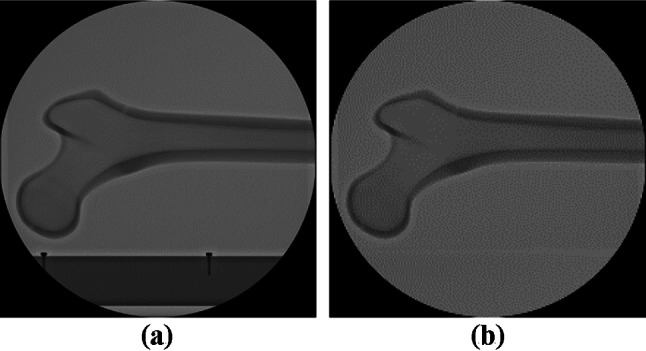

To verify the performance of the proposed method, X-ray image stitching experiments were conducted. Both the conventional and the proposed method were implemented in MATLAB (R2019a, Mathworks) using its toolbox. In the experiment, two types of test images were used: X-ray images of the caprine tibia and the human femur [40]. In the X-ray image of the human femur, anteroposterior (AP), and lateral (LAT) views of the image were used. In the X-ray images of the caprine tibia, the intact and fractured tibia states were used. As shown in Fig. 3, the fractured tibia was from a cadaver, and the intact tibia was a phantom. In addition, to reflect the conditions in an actual operation, fixation pins and the fixation plate, which are indispensable for fracture surgeries, were included in the X-ray images of the fractured tibia.

Fig. 3.

Test images used in the experiments. (a) X-ray images of a human femur (LAT view). (b) X-ray images of a human femur (AP views). (c) X-ray images of a caprine tibia (fracture). (d) X-ray images of a caprine tibia (with fixation pins). (e) X-ray images of a caprine tibia (with a fixation plate). (f) X-ray images of a caprine tibia (phantom)

The test images were simulated X-ray images from the C-arm. The X-ray images were generated following user interventions based on the manual adjustment of the overlap region. Considering the effect of the overlap region, it must be noted that the overlap between the second and third input images in each test image set was narrower than the overlap between the first and second input images. The results of the X-ray image stitching methods performed on the test images in Fig. 3 are shown in Fig. 4. SURF, SIFT, ORB, BRISK, KAZE, and the hybrid method (which combines SIFT and SURF), were used as the conventional methods of X-ray image stitching, and these were compared with the proposed method.